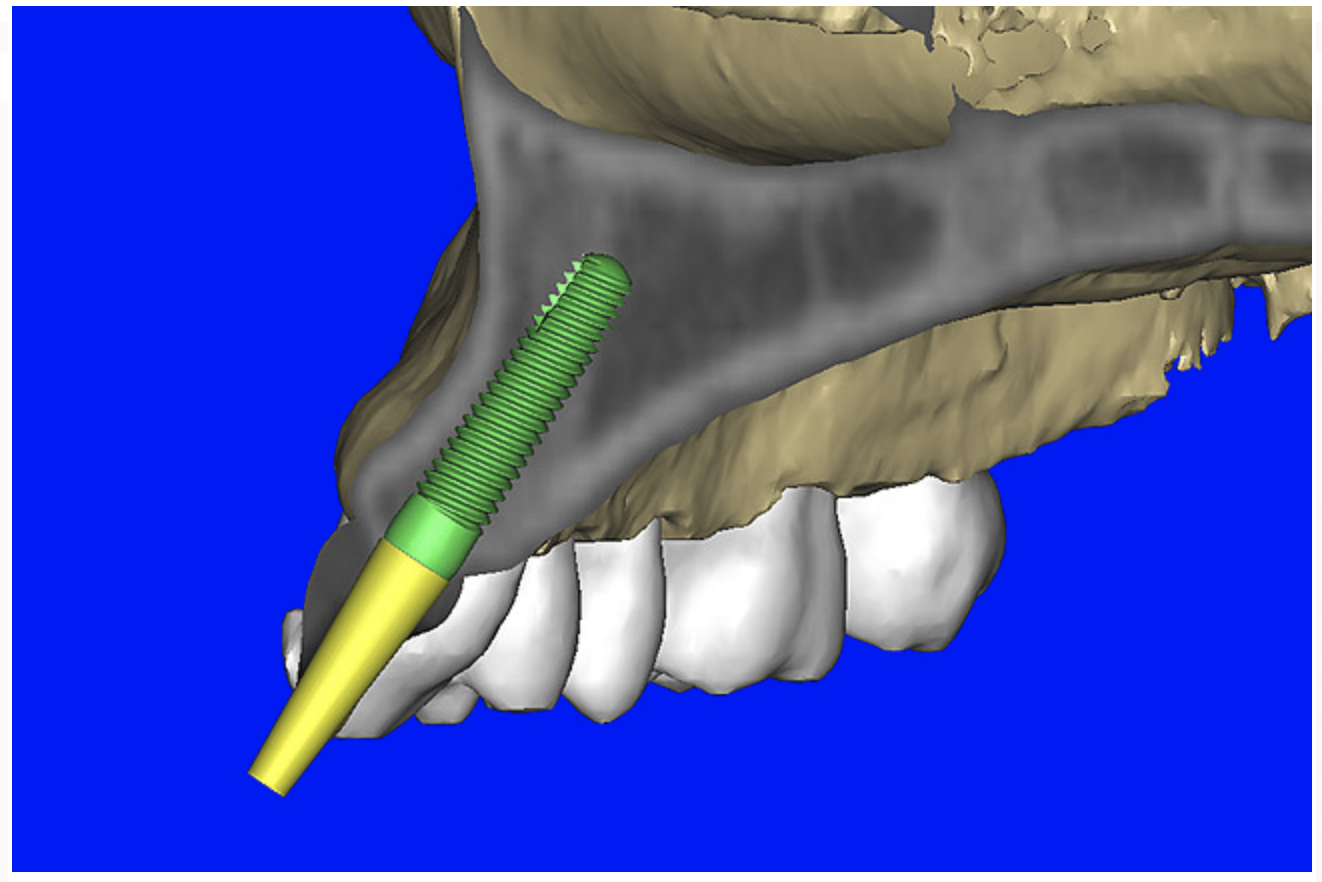

After the basic plan had been established, it was re-evaluated using interactive 3D images. The reconstructed 3D view of the maxilla clearly illustrated the extent of the bilateral facial concavities, and the root eminences of the adjacent and posterior teeth (Figure 7A). The placement of the virtual implants then was evaluated to ensure that the facial cortical plate was not perforated (Figure 7B). The implants were labeled individually as “7” and “10,” with the simulated yellow abutment projection indicating the facial-lingual inclination through the bone to the level above the incisal edge of adjacent teeth. The ability to gain a better understanding of these individual root forms can not be underestimated. The dental literature has suggested certain parameters for placing implants near teeth and implants next to other implants. However, there is little scientific 3D documentation to support these suggested rules.5-10 The use of an interactive treatment-planning software application permits closer scrutiny of previously difficult-to-visualize areas, and can now be used to redefine perceptions of spatial positioning of implants, especially when in close proximity to natural tooth roots, vital anatomy, and adjacent implants.27-29

Figure 7b  The 3D reconstruction showed (A) the facial concavities and root eminences, and allowed (B) for evaluation of virtual implant placement to ensure the facial cortical plate was not perforated.

Figure 7b